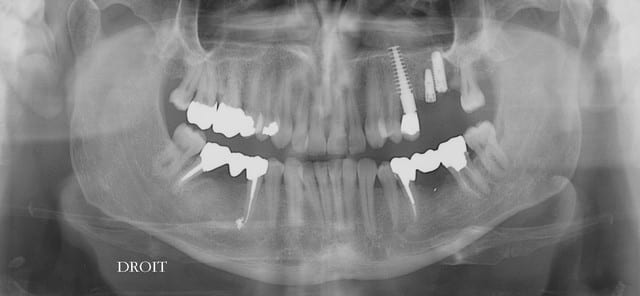

dommage je voulais poser le deuxieme 20mm mais la corticale etait pas d'accord pour laisser passer les osteotomes de Tatum alors adaptation.

les deux implants ne sont pas l'un sur l'autre mais un palatin et l'autre vestibulaire.